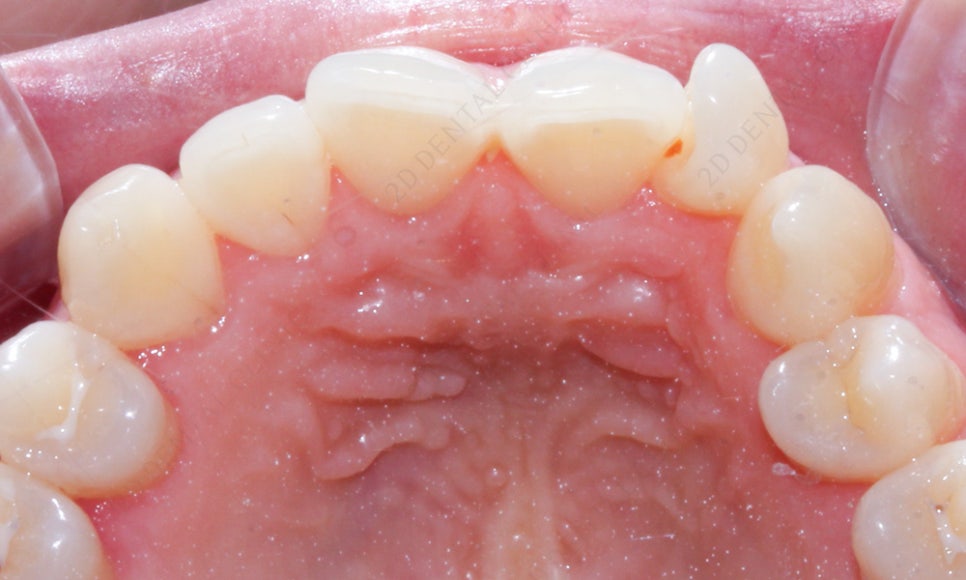

이렇게 앞니 옆에 치아가 돌아간 것은

측절치로 인한 상대적으로 덧니로 보이는 거기 때문에

앞니교정 or 투명교정으로도 효과가 좋습니다-:D

환자분의 치아를 진단한 결과

/90도 회전 측절치 개선

/전치부 배열을 위한 앞니교정